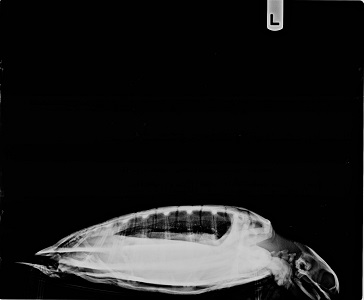

4.5 lb non-FP juvenile green

Minor plastron and carapace abrasions, as well as minor abrasions on chin and left side of beak. Parts of left caudal edge of carapace missing (old injury now healed). Missing tips of both rear flippers (old injuries, now healed)